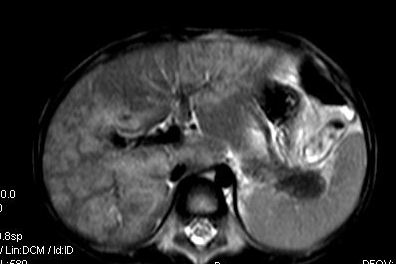

标题: V0176(MRI):小儿发热,肝脾大,肝内病变 [打印本页]

标题: V0176(MRI):小儿发热,肝脾大,肝内病变

5岁,2006年8月曾行阑尾炎手术,现发热半年